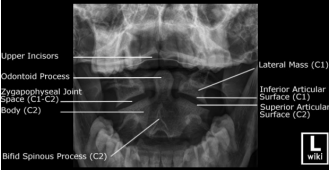

Incidências radiográficas de coluna cervical

5. Odontóide (trans-oral):

A

• Utilizada para visualizar C1 e C2 e processo

odontóide